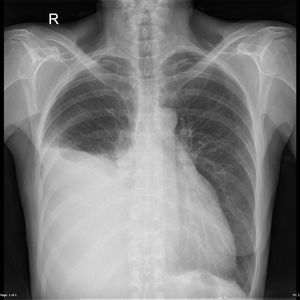

What’s your diagnosis?

It s pleural effusion which means collection of fluid with in pleural space...

Could it be atelectasis of the middle and lower lobe.. because i cant find any meniscus for it to be effusion